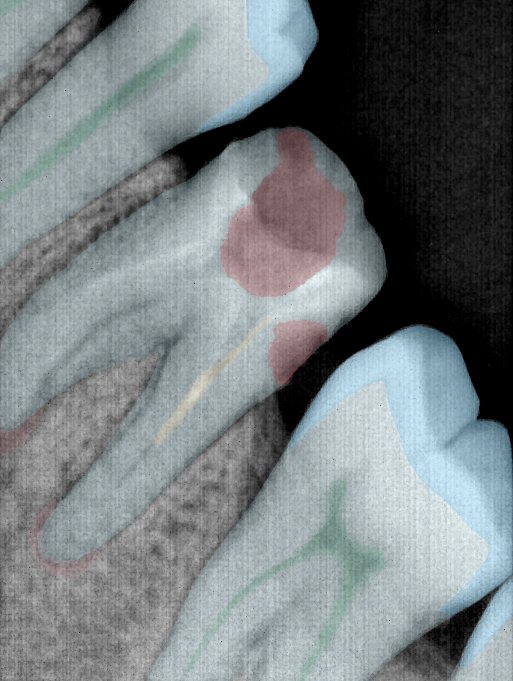

CR/DR 牙齿分割阶段记录

当前进展

- 完成了 CR/DR 牙齿相关分割训练

- 当前结果已经达到阶段预期,但仍有细节问题需要继续处理

相关测试

遇到的问题

- 训练过程中出现过 mask 下移问题

- 部分结果会出现 box 填充异常

- mask 边缘仍然有比较明显的锯齿感